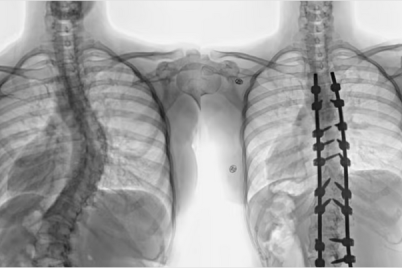

بفضل من الله تعالى وتوفيقه، أنهى مستشفى الدكتور سليمان الحبيب بالقصيم، معاناة شابة عشرينية مصابة بانحراف مضاعف ومتطور في...